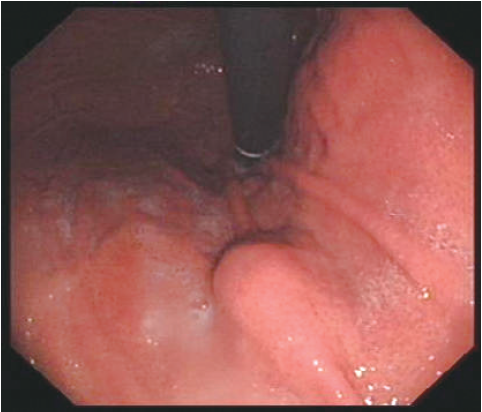

胃镜检查提示,胃底体交界小弯偏前壁见一约20mm×18mm大小半球形隆起,表面黏膜光滑,质韧(图1和图2)。

图1 胃镜:胃底体交界小弯偏前壁见一约20mm×18mm大小半球形隆起,表面黏膜光滑,质韧

图2 胃镜:胃底体交界小弯偏前壁见一约20mm×18mm大小半球形隆起,表面黏膜光滑、连续,质韧(反转观察)